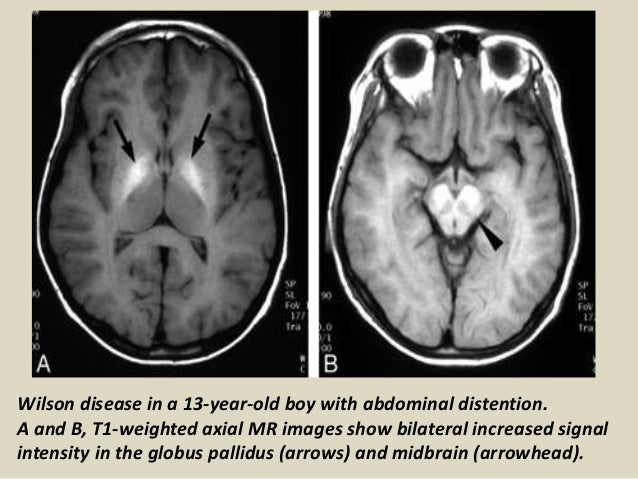

Wilson disease mri brain. MRI studies have identified focal abnormalities in the white matter pons and deep. Positive findings believed secondary to this condition were found in 15 subjects. Wilson disease hepatolenticular degeneration is an autosomal recessive defect in cellular copper transport.

6 8 Neurologic WD is one of the main forms of the disease. In Wilson disease WD T2T2weighted T2w MRI frequently shows hypointensity in the basal ganglia that is suggestive of paramagnetic deposits. It is currently unknown whether this hypointensity is related to copper or iron deposition.

Interval changes on follow-up MR imaging were also closely correlated with clinical findings and. MRI of the brain appears to be more sensitive than CT scanning in detecting early lesions of Wilson disease. The face of the giant panda sign panda sign of the midbrain or double-panda sign is a characteristic pandas face appearance in magnetic resonance imaging MRI images of people with Wilsons disease.

The neurologist was looking for typical symptoms. Wilson disease also known as hepatolenticular degeneration is a multisystem disease due to abnormal accumulation of copper. It is characterized by early onset liver cirrhosis with CNS findings most frequently affecting the basal ganglia and midbrain.

1 In addition a second miniature panda face can be seen in the high signal abnormality in the pons figure C. To describe the spectrum of brain abnormalities in Wilson disease hepatolenticular degeneration as depicted at magnetic resonance MR imaging and computed tomography CT and to relate these findings to neurologic and hepatologic abnormalities.

To describe the spectrum of brain abnormalities in Wilson disease hepatolenticular degeneration as depicted at magnetic resonance MR imaging and computed tomography CT and to relate these findings to neurologic and hepatologic abnormalities. Positive findings believed secondary to this condition were found in 15 subjects. It is found worldwide with a prevalence of approximately 1 case in 30000 live births in most populations. Thirty-eight patients with biochemically proven Wilsons disease underwent magnetic resonanceimaging MRI of the brain as well as neurological examinations. Fifty patients with Wilson disease participated in the cross-sectional. The face of the giant panda sign panda sign of the midbrain or double-panda sign is a characteristic pandas face appearance in magnetic resonance imaging MRI images of people with Wilsons disease. 1 In addition a second miniature panda face can be seen in the high signal abnormality in the pons figure C.